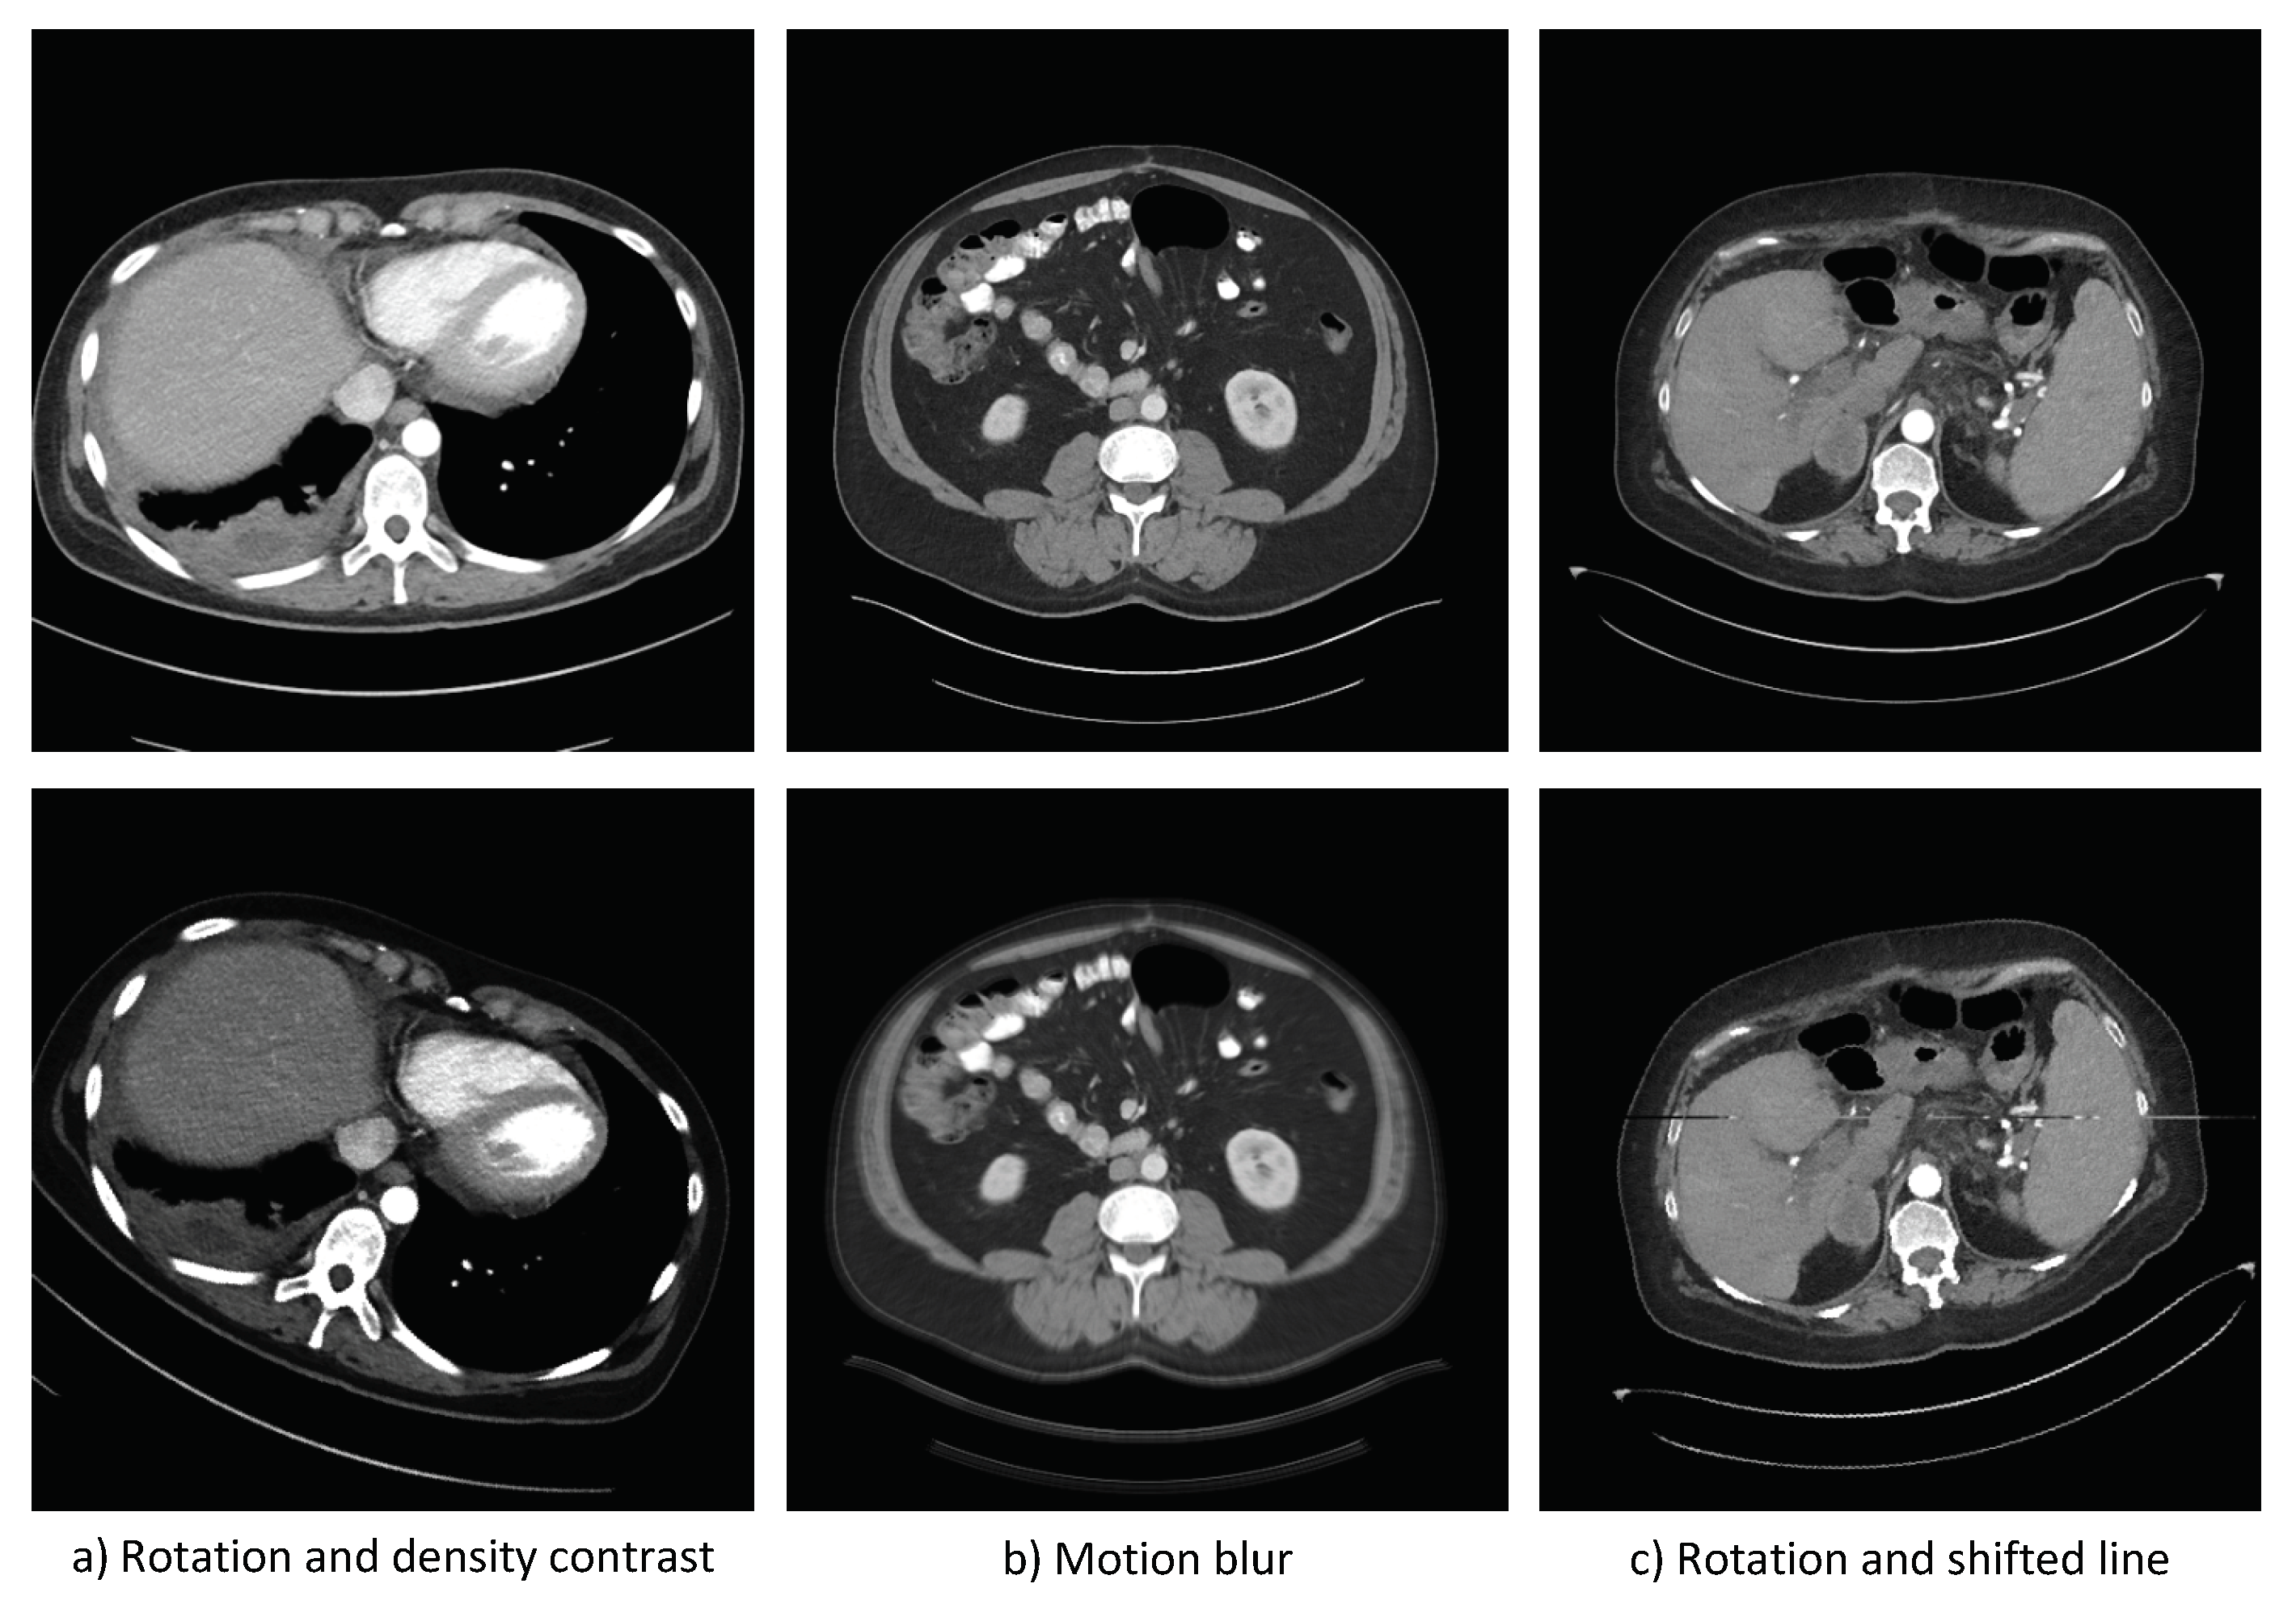

The first step is to determine the transformations to be applied to the images in the source dataset to generate the follow-up test cases. These transformations are then randomly applied to images from the source dataset in order to generate the follow-up test cases in proportions similar to the frequency of the target circumstances. We call this newly generated dataset of follow-up test cases, the target dataset. See Figure 6 for examples of source and follow-up test cases, for the MDS case.

Figure 6.

Examples of source test cases (source circumstances), on the top, and follow-up test cases (target circumstances), on the bottom, for the MDS case.